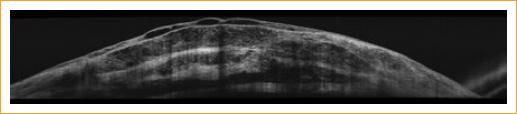

En la OCT del segmento anterior se apreciaba la ampolla conjuntival con líquido subyacente por microperforación escleral con adelgazamiento del tejido. Se le realizó una analítica completa en la que solo destacaron los niveles límite de eosinofilia (600/microlitro), el perfil de autoinmunidad (anticuerpos antinucleares, anticuerpos anticitoplasma de neutrófilo, factores de complemento, velocidad de sedimentación glomerular), hemograma y bioquímica resultaron normales (Figs. 3 y 4).

Figura 3 Tomografía de coherencia óptica del polo anterior del ojo derecho que revela el adelgazamiento escleral y la microperforación del tejido.

Figura 4 Tomografía de coherencia óptica del polo anterior del ojo derecho que revela el adelgazamiento escleral y la microperforación del tejido.